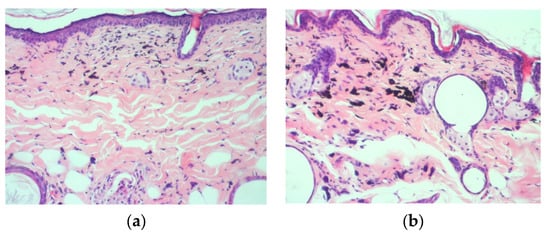

Our results from skin biopsies verifying the existence of PMU colorants in both areas of mice backs (treated with discoloration agents and untreated without using any discoloration procedure). This observation is obvious in both Figure 2a,b which is a biopsy from skin with the lush pink colorant. In the treated area (Figure 2a), the discoloration process with Pelargonium zonale was used with the PMU machine. In Figure 2a, we can see skin tissue with common characteristics as in Figure 2b, which is an untreated area without any discoloration process on the skin. There is no inflammation while the thickness of the skin is the same in both cases which shows no side effects from the whole process. The good condition of the skin in the treated and untreated areas (Figure 2a,b) reveals that the discoloration process and plant-based materials do not damage the skin. The amount of PMU colorants cannot be measured as it can be seen in both figures.

Skin biopsies from treated area (a) with Pelargonium zonale (Pe) and untreated area (b) from the colorant lush pink, 73 days after PMU application. In (a), there have been 8 discoloration procedures for PMU removal while (b) has not been treated with discoloration procedure. PMU colorants can be observed in both figures (10× hematoxylin/eosin).